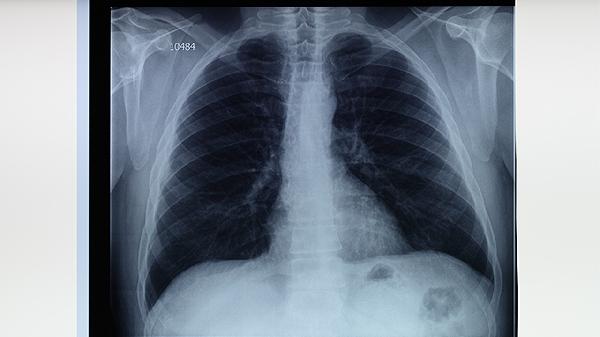

肺结核患者服药期间应保持均衡饮食,适量增加优质蛋白和维生素摄入,避免酒精及高嘌呤食物。建立用药提醒制度确保按时服药,使用专用药盒分装每日剂量。定期复查胸部影像学和痰菌检查,治疗全程需6-9个月。出现药物不良反应时不可擅自停药,应及时与主治医生沟通调整方案。保持居住环境通风良好,咳嗽时掩住口鼻,痰液需消毒处理。适当进行呼吸功能锻炼,但避免剧烈运动导致过度疲劳。